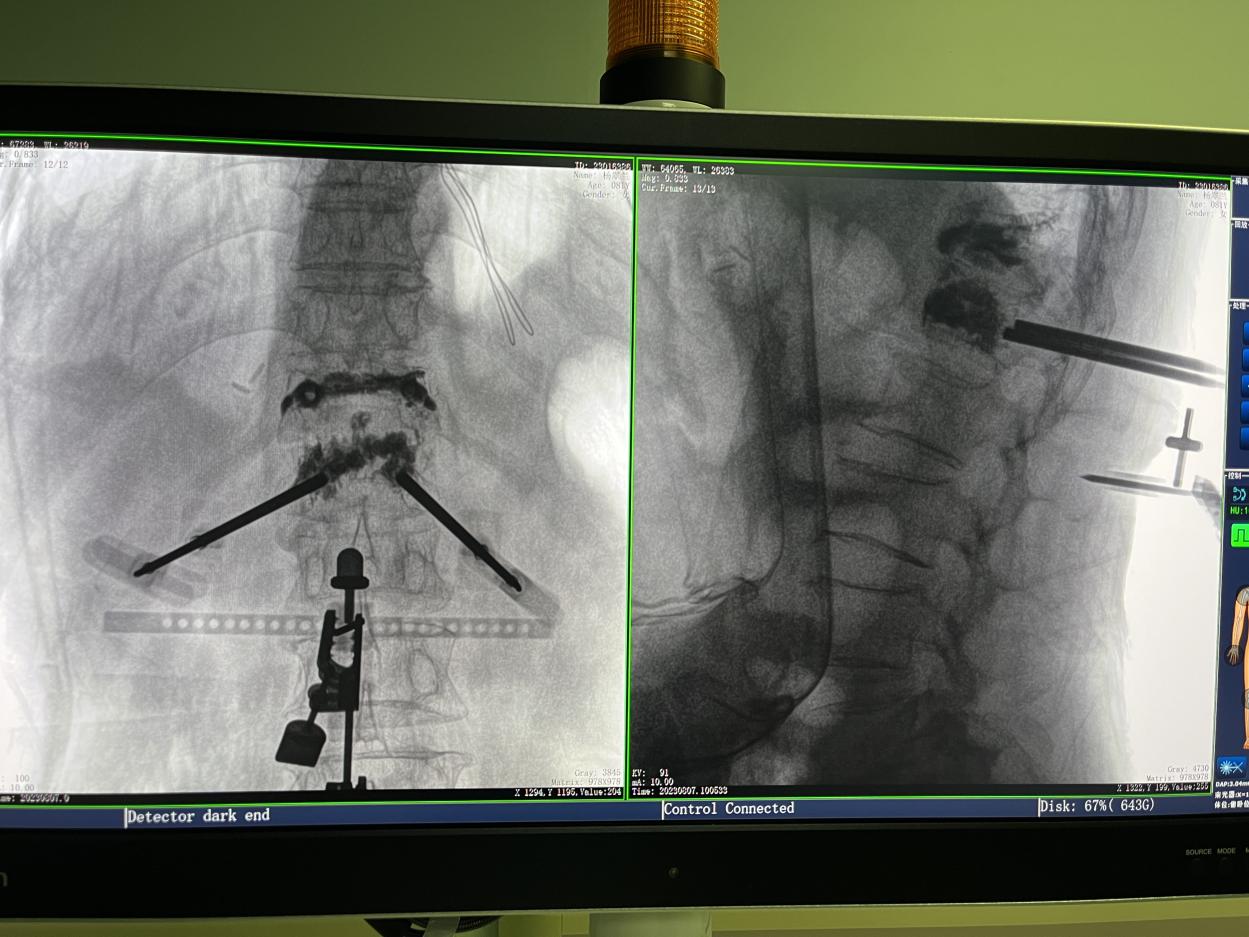

骨科機器人手術-術后影像

4.微創(chuàng)皮膚切口

傳統(tǒng)的開放式手術需暴露手術可見視野,以便醫(yī)生獲得更多的判斷信息,手術創(chuàng)口大,術后恢復時間長。而在骨科機器人輔助的微創(chuàng)手術中,手術創(chuàng)口僅為1~2厘米左右的小切口,創(chuàng)傷小、恢復快。